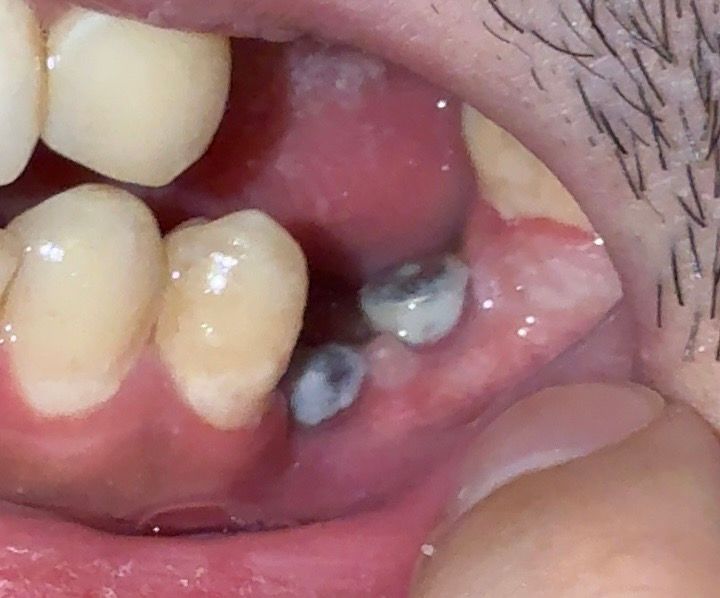

사진에서 보시면 아래쪽 잇몸이 많이 꺼져있는것 같은데 보철물 부착을 할 수 있는지 궁금합니다

• 3번 째 사진

치조골이 약하거나 없는 부분은 임플란트 수술을 했을 때 아래쪽으로 꺼져 보일 수 있습니다. 이런 부분은 보철물을 제작할 때 내려가 있는 부분에 맞게 보철물을 만들기 때문에 문제가 되지 않습니다.

큰 문제는 없을 것 같습니다 다만 본뜬 것과 잇몸 높이차가 크다면 추후 위생관리에 불리할 수 있습니다